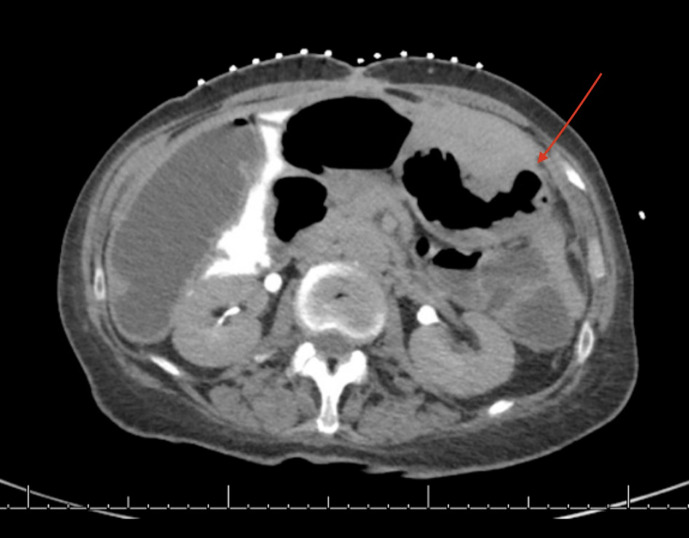

Introduction: We report the case of a 60-year-old female with a history of perforated gastric ulcer, abdominal abscesses, enterocutaneous fistula, and small bowel obstruction requiring durable gastric decompression prior to delayed fistula takedown. The patient had contraindications to or failed attempts at traditional gastrostomy approaches (surgical, endoscopic, interventional radiology).

Case report: Gastrostomy was successfully performed via a novel technique combining interventional radiology and endoscopic placement.